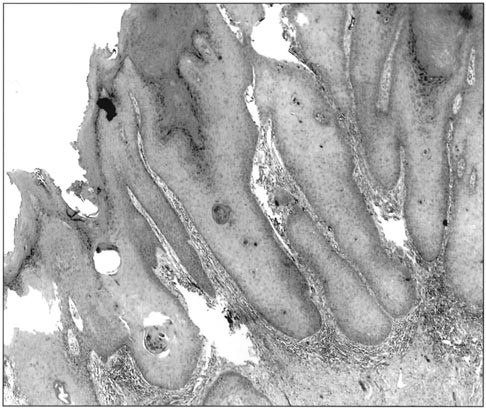

Grade 1 superficially invasive squamous cell carcinoma.